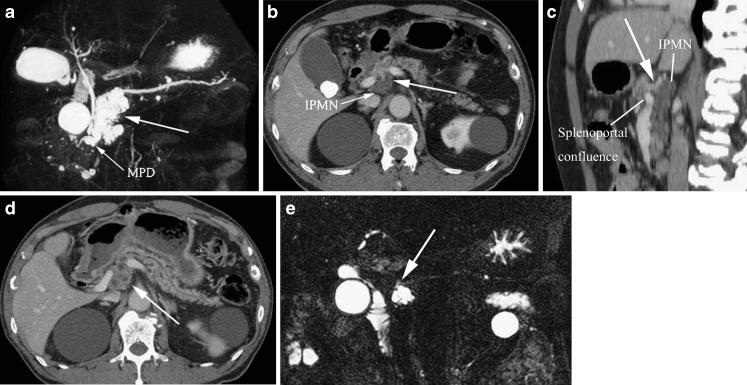

To evaluate the prevalence of circumportal pancreas (CP) and any coexisting anomaly. In addition, three cases of surgically confirmed CP are presented. METHODS: The study group consisted of 317 consecutive potential liver transplant donor candidates who had undergone thin-section MDCT studies for the evaluation of vascular anatomy. MDCT images were retrospectively reviewed to assess the presence or absence of CP. If CP was present, the transverse diameter of the aberrant pancreatic tissue was measured on axial images, and the course of the main pancreatic duct (MPD) was classified into ante-portal (normal) or retro-portal. In addition, the prevalence of variant hepatic arterial anatomy was compared between cases with and without CP. RESULTS: Eight of 317 liver transplant donor candidates (2.5%) were found to have CP at CT. The transverse diameter of the aberrant pancreatic tissue ranged from 5 to 18 mm (mean ± SD: 10 ± 4 mm). One of eight (12.5%) showed the MPD to be retro-portal. A variant hepatic artery was noted in two of the of eight (25%) patients, which was similar to the finding for those without CP [72 out of 309 (23%)]. CONCLUSION: The prevalence of circumportal pancreas was 2.5%.